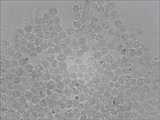

Fig. 2 is that liver cancer cancer patient MICRORNA-21 expresses picture in the embodiment of the invention.

20 of hepatocarcinoma patients, 20 of high risk population's (hbv-liver cirrhosis), 20 of normal control groups.Take out all people's to be checked peripheral blood 3-5 milliliter (separation white corpuscle) and do in situ hybridization.The result representes that all cancer patients MICRORNA-21 expression amounts are high, and cell dyeing is dark; The high risk population expresses slightly and reduces, decimal dyeing; Normal control group MICRORNA-21 expression amount is low, the dyeing of cell minority, and concrete outcome is seen Fig. 2, Fig. 3, Fig. 4.